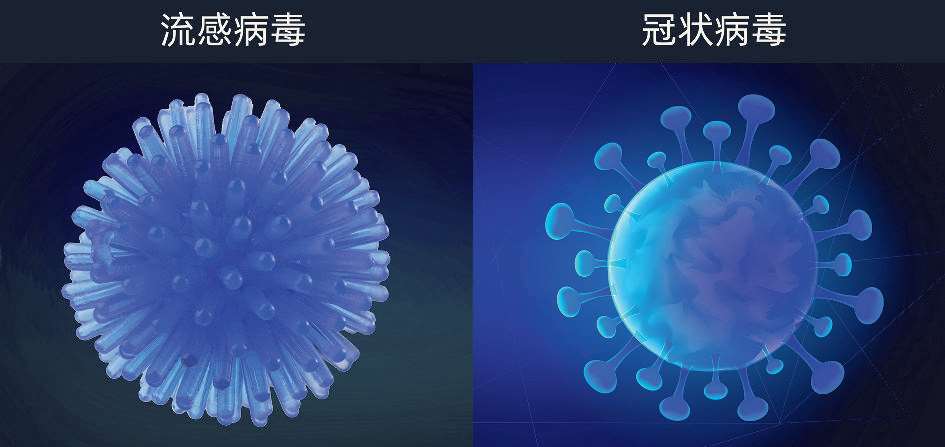

冬春季呼吸道疾病病原体以流感病毒为主,一般每年在10月下旬开始进入流感冬季流行期,同期也会有其他呼吸道疾病交替或共同流行,包括鼻病毒、肺炎支原体、新冠病毒、呼吸道合胞病毒、腺病毒、副流感病毒等。

流感是流行性感冒的简称,是由流感病毒引起的急性呼吸道传染病。病毒由包膜、基质蛋白及核心组成。根据流感病毒核蛋白的抗原性,一般将其分为甲(A)、乙(B)、丙(C)三型。

冠状病毒是在自然界广泛存在的一类病毒。病毒外有脂肪膜,膜表面有三种糖蛋白:刺突糖蛋白(是受体结合位点和主要抗原位点)、小包膜糖蛋白及膜糖蛋白。

2019新型冠状病毒(2019 nCoV,引发新型冠状病毒肺炎COVID 19)是目前已知的第7种可以感染人的冠状病毒,其余6种分别是HCoV 229E、HCoV OC43、HCoV_NL63、HCoV_HKU1、SARS_CoV(引发重症急性呼吸综合征)和MERS CoV(引发中东呼吸综合征)。